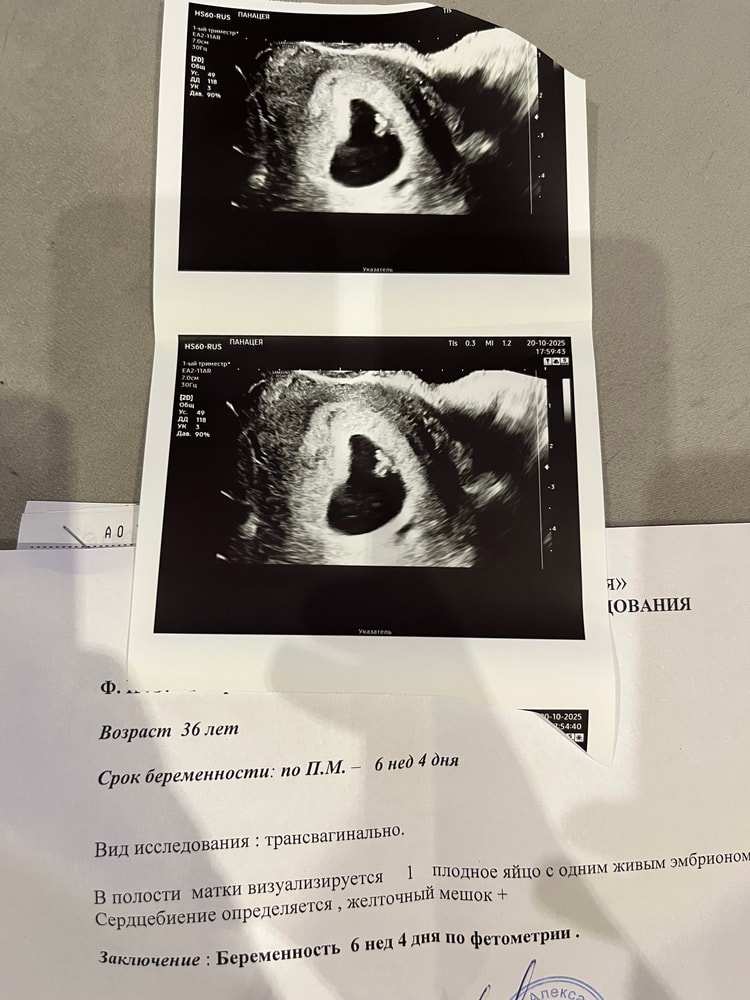

оличкин в Зачатие 2 месяца УЗИ 6,4 малыш с нами УЗИ Всем добрый вечер. Сегодня ходила на УЗИ, по последним мес срок 6,4, по размерам сказала совпадает на 6,4. Сердечко стучит 🤭. Сказала все хорошо 🙂. Ничего что ПЯ такой капелькой? Описание конечно скромное, первый раз такое вижу. Посмотрите еще 20 записей на эту тему Отменить Ответить Наталья Нормально. У меня как седло было. 20.10.2025 Ответить ЖТ НА УЗИ УЗИ в 6 недель 3 дня Чаты Беременных Выберите чат: Январята-2026 Февралята-2026 Мартята-2026 Апрелята-2026 Майчата-2026 Июнята-2026 Июлята-2026 Августята-2026